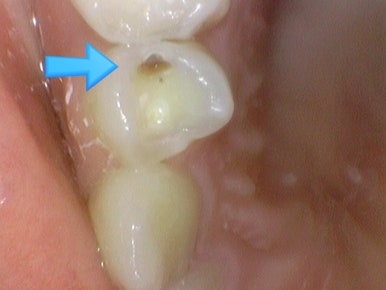

사진의 깨진 치아의 사진상 하단에 위치한 치아는 동일 치아이나

왼쪽사진에서 보이던 충치가 치료를 하지 않았는데도 오른쪽 사진에서 잘 보이지 않는데요

침 때문에 잘 보이지 않는 상태입니다.

따라서 충치 검진은 치과에서 치과전용체어에서 에어를 불어서 정확히 확인하는게 맞습니다.

일반 가정에서 눈으로 볼 때는 침때문에도 충치가 잘 안보이는 경우도 많습니다.

치과에서 치과의사가 눈으로 보는것 + 엑스레이로 모두 확인해야합니다.